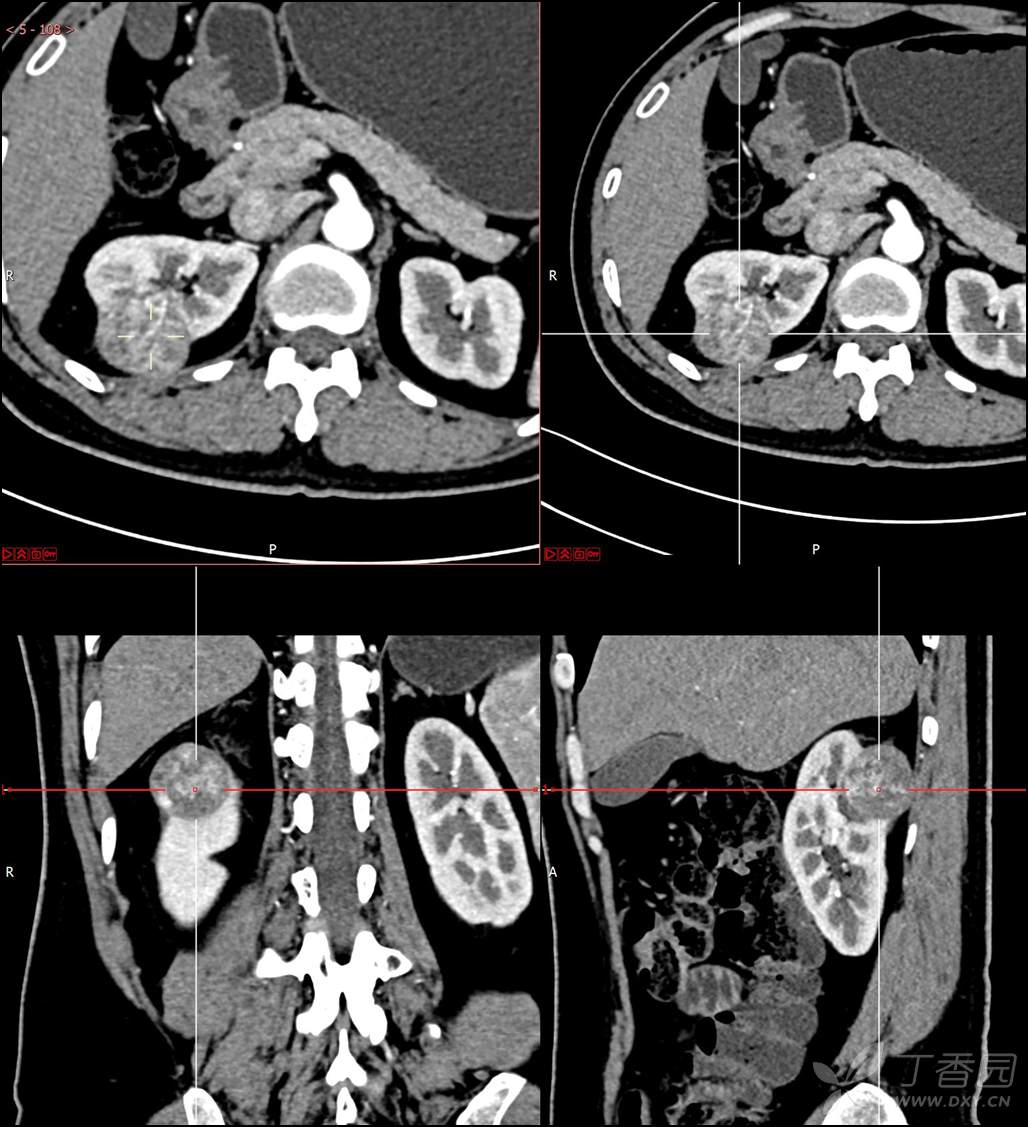

主诉:查体发现右肾肿物2月余

简要病史:患者2月余前于我院行健康查体,胸部(肺)CT平扫示:右肺中叶结节并右侧阻塞性肺炎;左肺上叶小结节;右肾占位。自诉无腰背部疼痛不适,无尿频、尿急、尿痛,无肉眼血尿,无恶心呕吐,无心悸、胸闷,无发热、寒战等不适,建议进一步检查。现患者为求进一步诊治于为我院就诊,建议手术治疗,门诊遂以“肾肿物(右)”收入院。患者自发病以来神志清,精神可,饮食可,睡眠欠佳,大便正常,体重近期无明显增减。